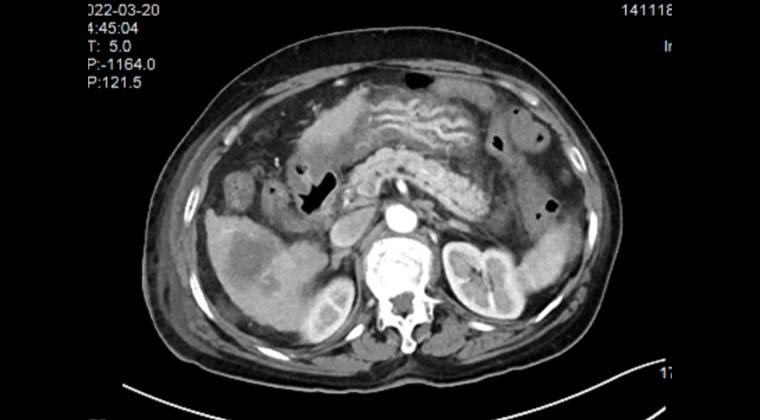

Пациент: женщина, 70 лет, злокачественная солидная опухоль печени, очаг расположен рядом с кишечником.

Процедура: выполнена под общим наркозом. Через чрескожный прокол были размещены два электрода, охватывающие очаг, после чего проведена абляция. Во время процедуры сила поля оставалась стабильной, ток заметно увеличился, абляция прошла успешно.

После процедуры: на контрольной КТ с контрастированием границы очага четкие, зона абляции без выраженного усиления.

КТ с контрастированием перед процедурой